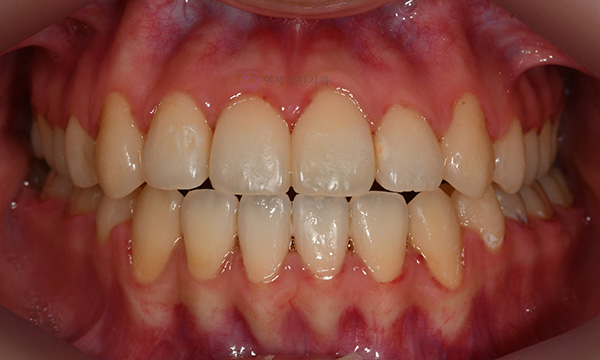

위 환자분은 치아 중심선이 맞지 않는다는 주소로 치과에 내원하셨습니다. 미소시 사진을 보면 위 치아도 오른쪽(사진 상 왼쪽)으로 틀어져 있고, 아래 치아도 왼쪽(사진 상 오른쪽)으로 틀어져 있었습니다. 그리고 양쪽 입꼬리 근육의 활성도도 차이가 있어서, 웃었을 때 왼쪽 입꼬리가 오른쪽보다 덜 올라가서 비대칭이 더 강조되어 보였습니다.

2020.7

치아 중심선의 차이를 개선하고, 얼굴의 중심과 치열의 중심을 맞춰주기 위하여 오른쪽 아래 작은 어금니를 하나만 발치하여 그 공간으로 아래 치열을 오른쪽으로 돌려주고, 위 치열은 전체적으로 왼쪽으로 치열을 이동시켜서 중심선을 맞추어 주었습니다.

2022.6

위 아래 치아의 중심선이 일치하고 좌우 어금니의 교합도 잘 맞춰졌습니다. 좌우 입꼬리 올림근 활성도의 차이는 남아있음에도 얼굴의 중심과 위 아래 치아의 중심이 일치하여 미소시에도 교정 전보다 훨씬 자연스러운 미소를 짓게 되었습니다.